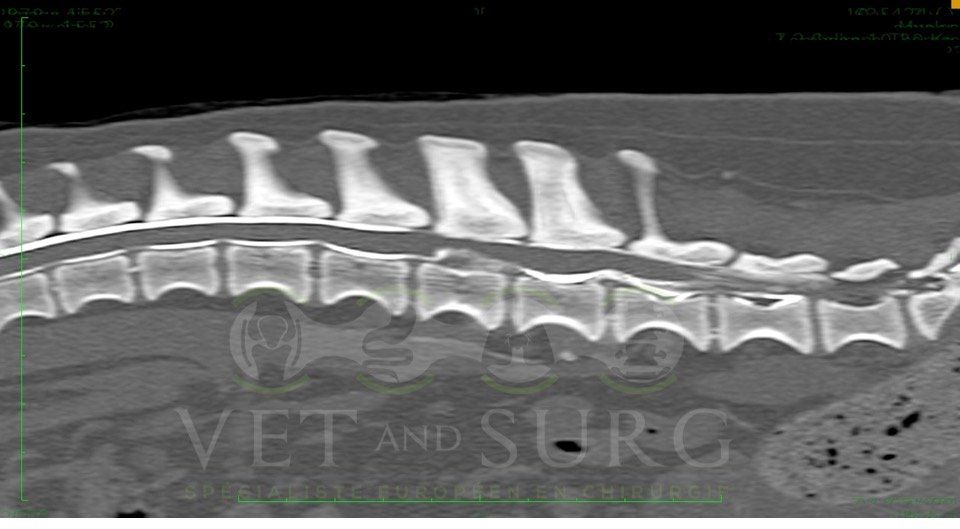

Hernie discale chez un bouledogue de 5 ans

Georges est présenté pour une paralysie des deux membres postérieurs.

Le scanner du rachis révèle une hernie discale en L3-L4 comprimant sévèrement la moelle épinière.